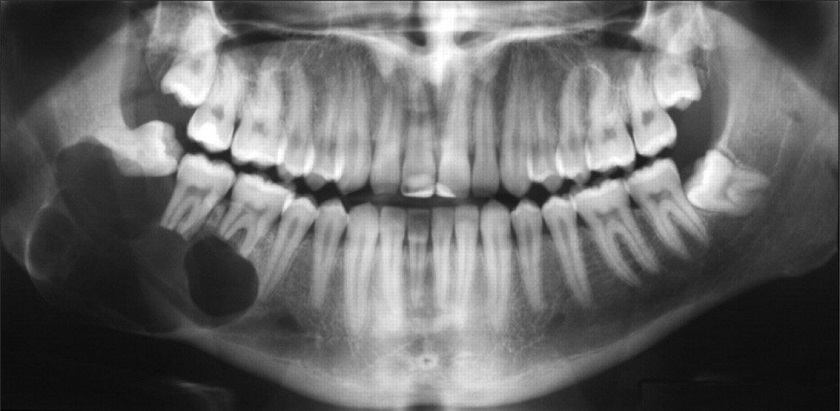

U nang

Đây là trường hợp răng khôn mọc trong một túi u bên trong xương hàm. Túi u này có thể chứa đầy chất dịch, tạo thành u nang có thể làm tổn thương đến xương hàm, răng và dây thần kinh. Đôi khi một khối u có thể phát triển từ u nang. Biến chứng này có thể dẫn đến việc cắt bỏ mô và xương.

U nang răng